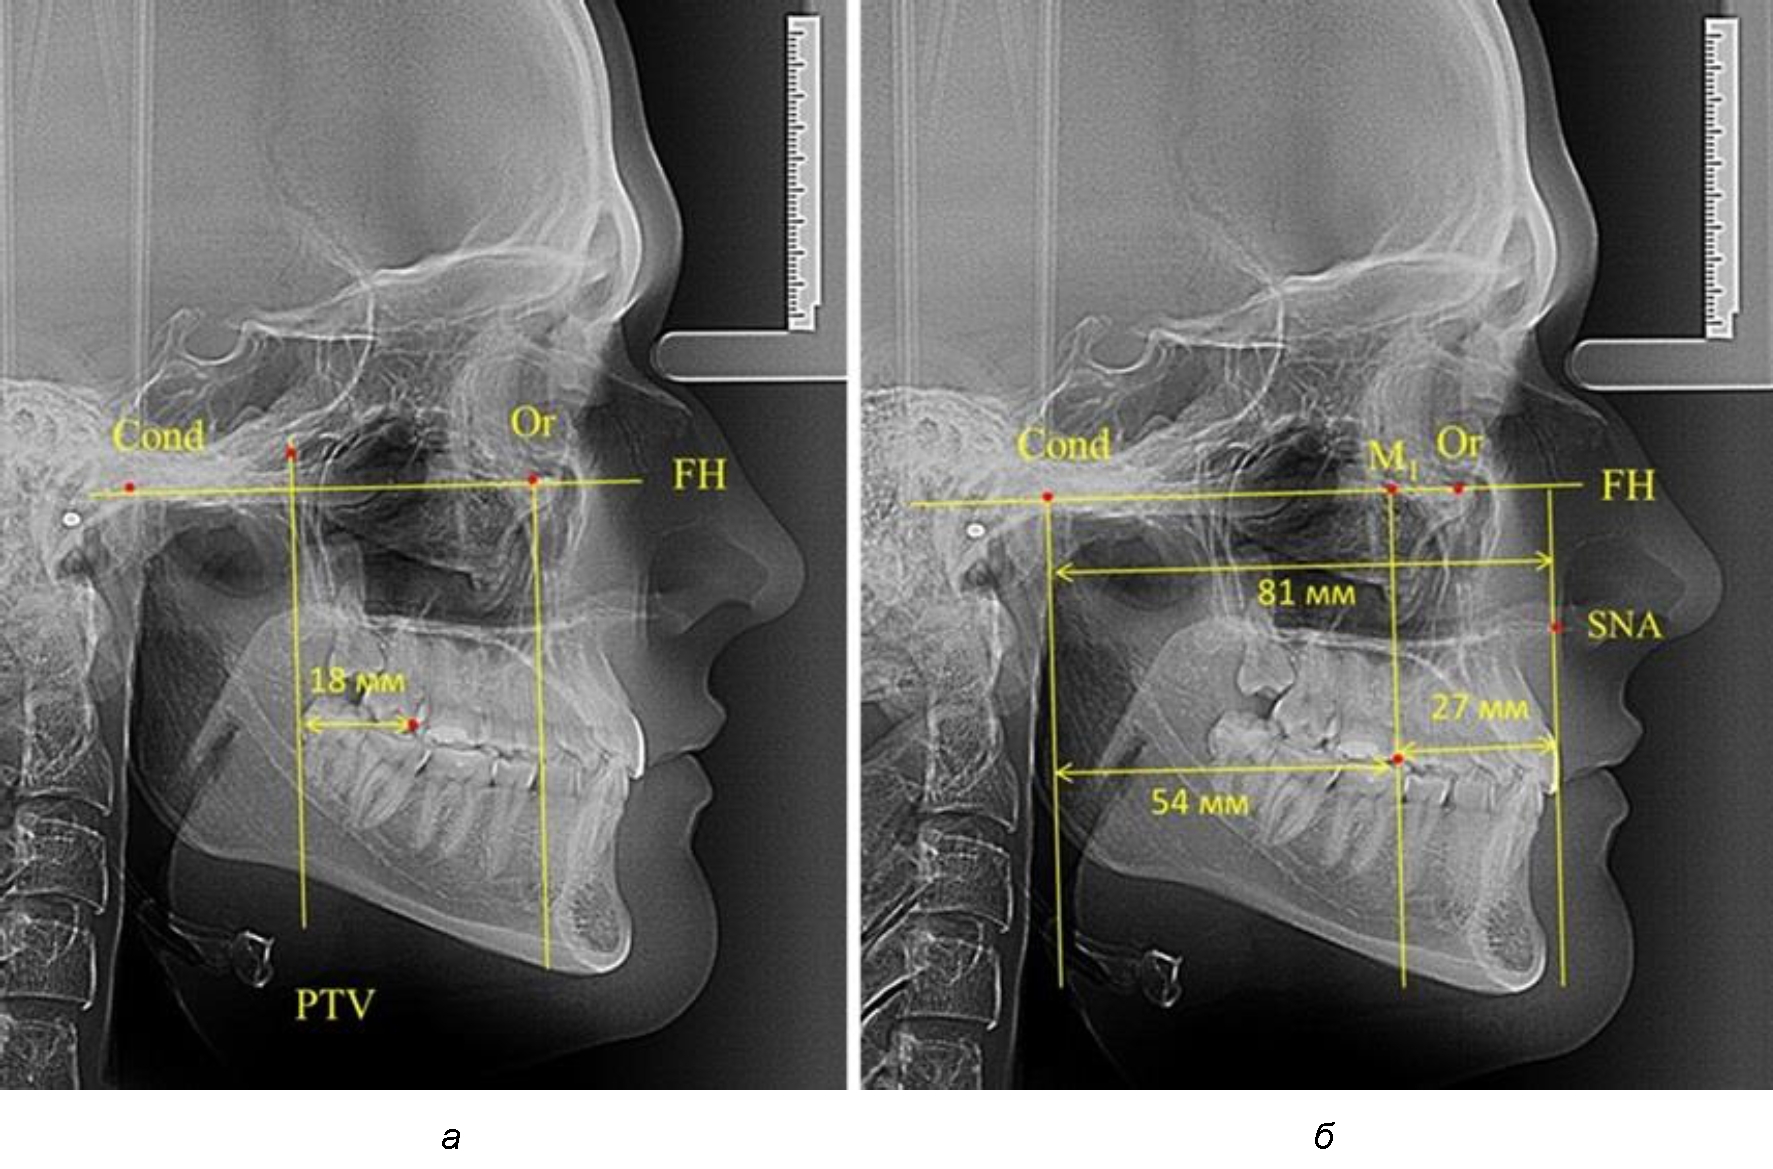

Второй частью исследования был анализ положения первых постоянных моляров в различные периоды сменного прикуса. На телерентгенограммах детей периода прикуса молочных зубов дистальная поверхность зачатка первого постоянного моляра отстояла от крыловидной вертикали на величину, составляющую около 7 мм, что было близким по значению к данным R. E. McDonald. Сагиттальный размер гантического отдела составлял около 60 мм, а его отношение к кондилярно-молярной глубине – 1,5 (рис. 4).

Рис. 4. Особенности положения первых моляров по R. E. McDonald (а) и по предложенному методу (б) у ребенка 4 лет